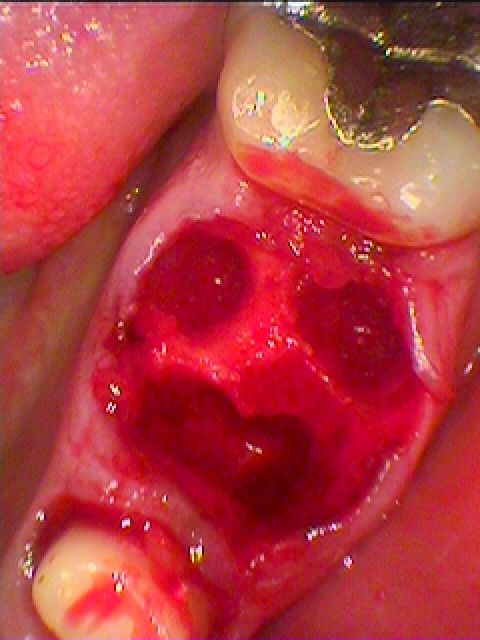

即時インプラント埋入を行っていきました

隙間には骨補填材を転入しています